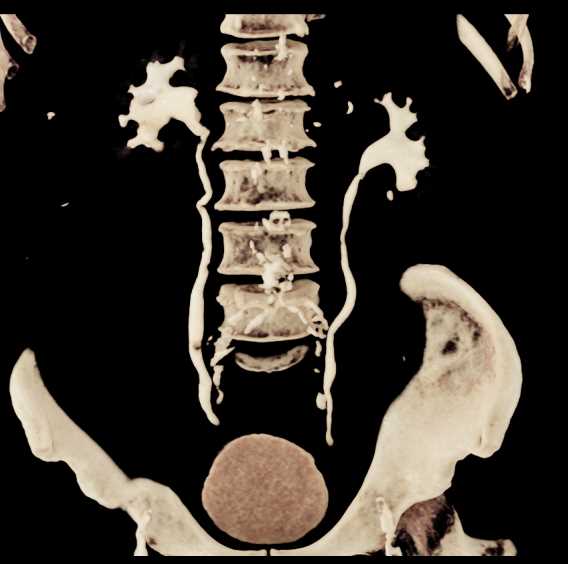

Transitional Cell Carcinoma Right Kidney and Bladder